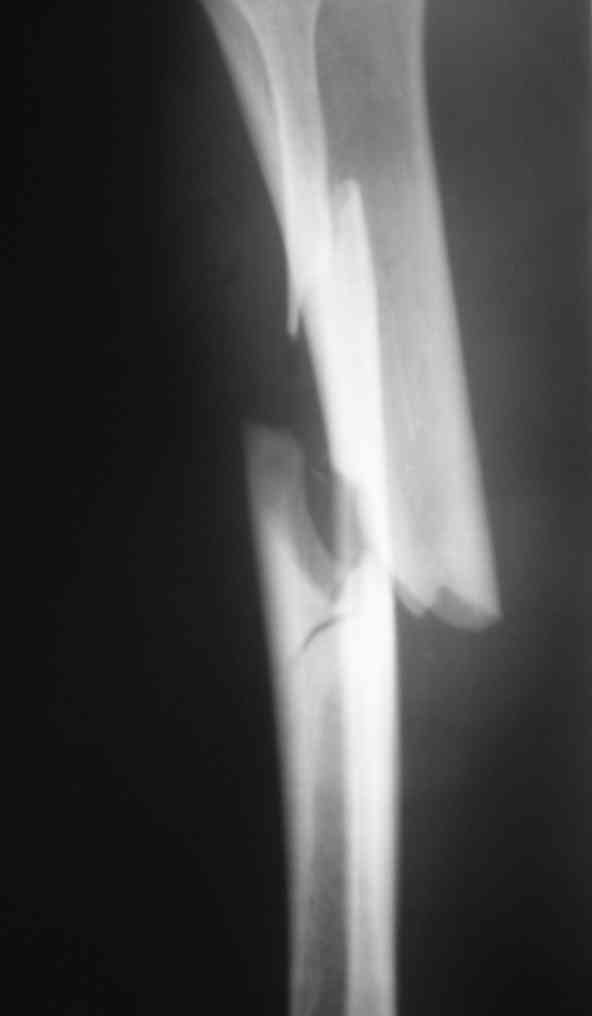

Дорогой Александр. Имею скромный опыт использования системы Fixion при переломах плеча, бедра и тибии. Всего 18 наблюдений с сентября 2006 г. Результаты отличные. Гвоздь индивидуален для каждого медуллярного канала. Легко имплантируется как в узкий, так и в деформированный канал. Это позволяет применять метод интрамедулярного остеосинтеза без ненужных потерь времени операции, флюороскопии и реально снижает крвопотерю и операционный риск. Удаление происходит без проблем. Особенно интересны больные с ипсилатеральными переломами бедра и голени.

Да, спасибо за интересные иллюстрации. Получилось очень симпатично. На большеберцовой кости непременно надо было винты? Там же был торцовый упор, перелом в средней трети?